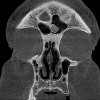

Залив сBCT. Томографическая компьютерная томография вспомогательных пазух, выполненная с использованием рентгеновского лучевого направления. Это позволяет получить трехмерное цифровое изображение исследуемой области в реальном масштабе, благодаря чему специалист имеет возможность исследовать анатомические особенности и патологические процессы в пазухах. Показания к КЛКТ включают диагностику синусита (в том числе стоматологической этиологии), полипов околоносовых пазух, переломов пазух, а также планирование манипуляций и операций на ларингологических органах и контроль их эффективности. КЛКТ околоносовых пазух имеет ряд преимуществ перед стандартной рентгенографией и КТ: меньшая радиационная нагрузка, отсутствие ошибок сканирования и короткое время лечения.

Из-за значительной дифференциации анатомического строения околоносовых пазух у разных людей и в разном возрасте испытуемых нет стандартизированных результатов КЛКТ. Как правило, размеры и симметрия (с выпаренными заливами) полостей, наличие или отсутствие серьезных аномалий их развития описываются. Особое внимание при сBCT придаточных пазух носа уделяется слизистым оболочкам, которые выстилают внутреннюю поверхность пазух - их утолщение может указывать на воспаление различного генеза, а нерегулярность может быть признаком ракового процесса. Для более точного изучения риска развития рака можно использовать контрастные методы.